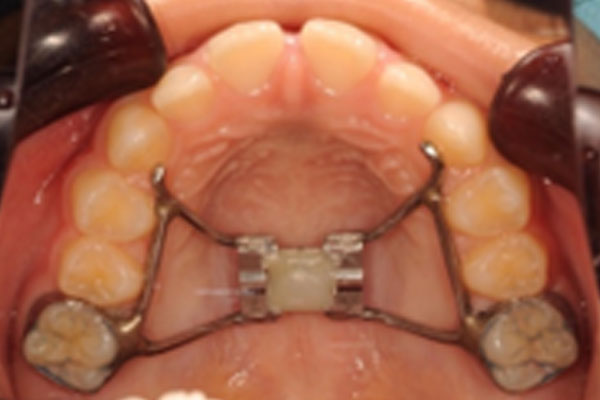

上顎に付ける固定装置です。装置の中央に装着されたネジを回して顎を拡大し、顎の成長をコントロールします。